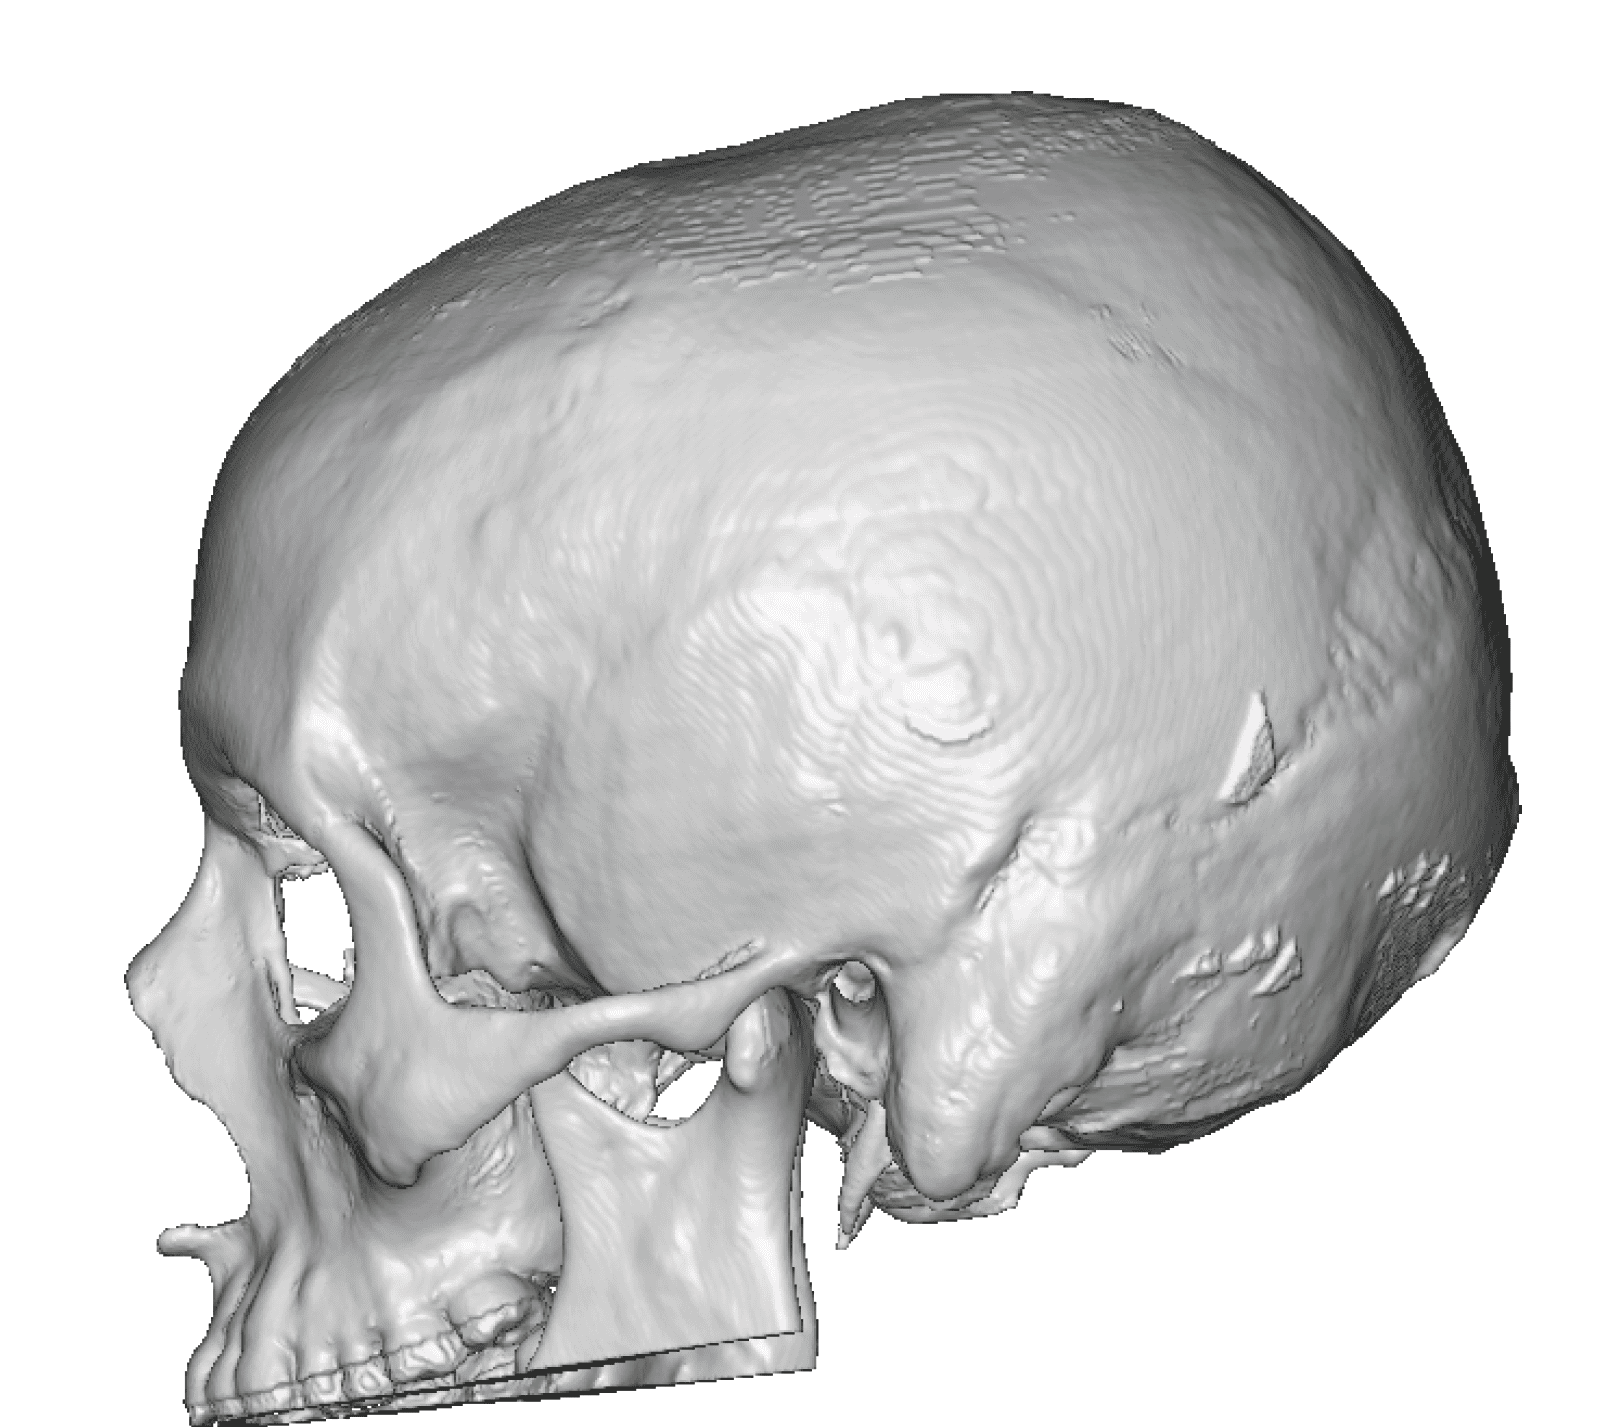

Patient 49

Desire for further skull augmentation after a primary skull implant.

Five years after an initial custom skull implant placement a new custom skull implant that increased the volume by 35% was placed.

Desire for further skull augmentation after a primary skull implant.

Five years after an initial custom skull implant placement a new custom skull implant that increased the volume by 35% was placed.